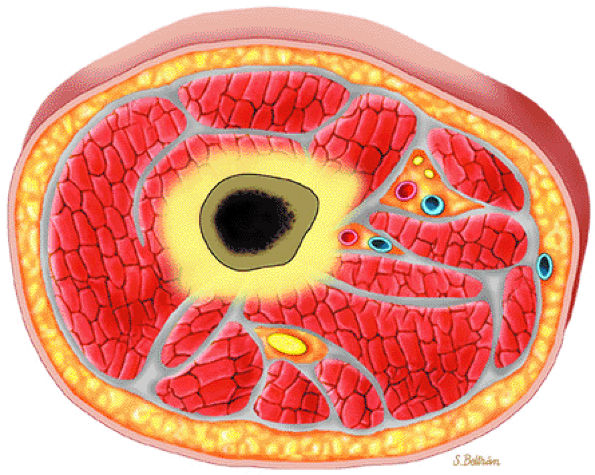

FIGURE 13.13 ● Axial graphic illustration demonstrates focal abnormal bone marrow of the femoral metaphysis with surrounding edema.